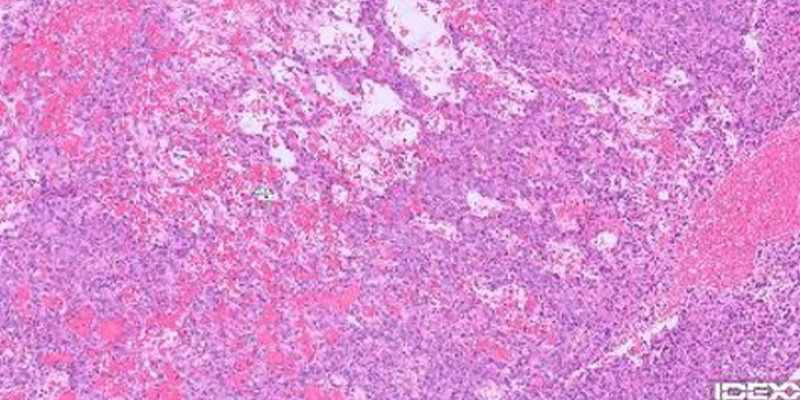

Histology slide showing invasive neoplasm – comprising dense streams of neoplastic cells rarely forming irregular blood-filled channels on a dense fibrovascular stroma

spindle cells were observed within the sample which caused concern this could be neoplasia. A further, deep tissue biopsy was necessary to confirm diagnosis. This was performed and urgent re-testing of the cells organised. The results showed highly malignant haemangiosarcoma. Without treatment, the risk of metastases is high and rapid mortality is almost certain. Both surgery and chemotherapy are recommended to treat and reduce occurrence of further tumours. It is important that a wide margin is included in the removal; or complete removal of malignant cells remain, reestablish and render the surgery ineffective.